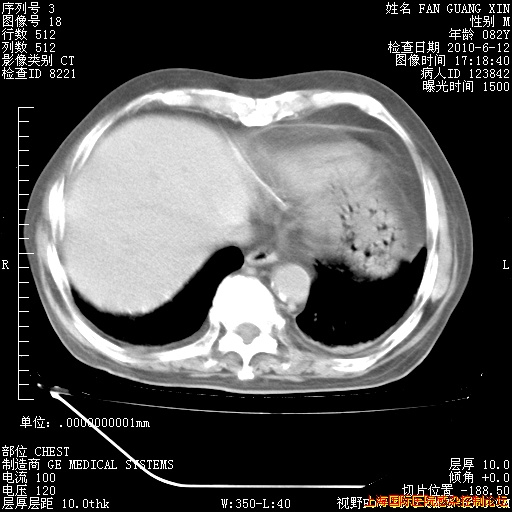

6月12日纵膈窗